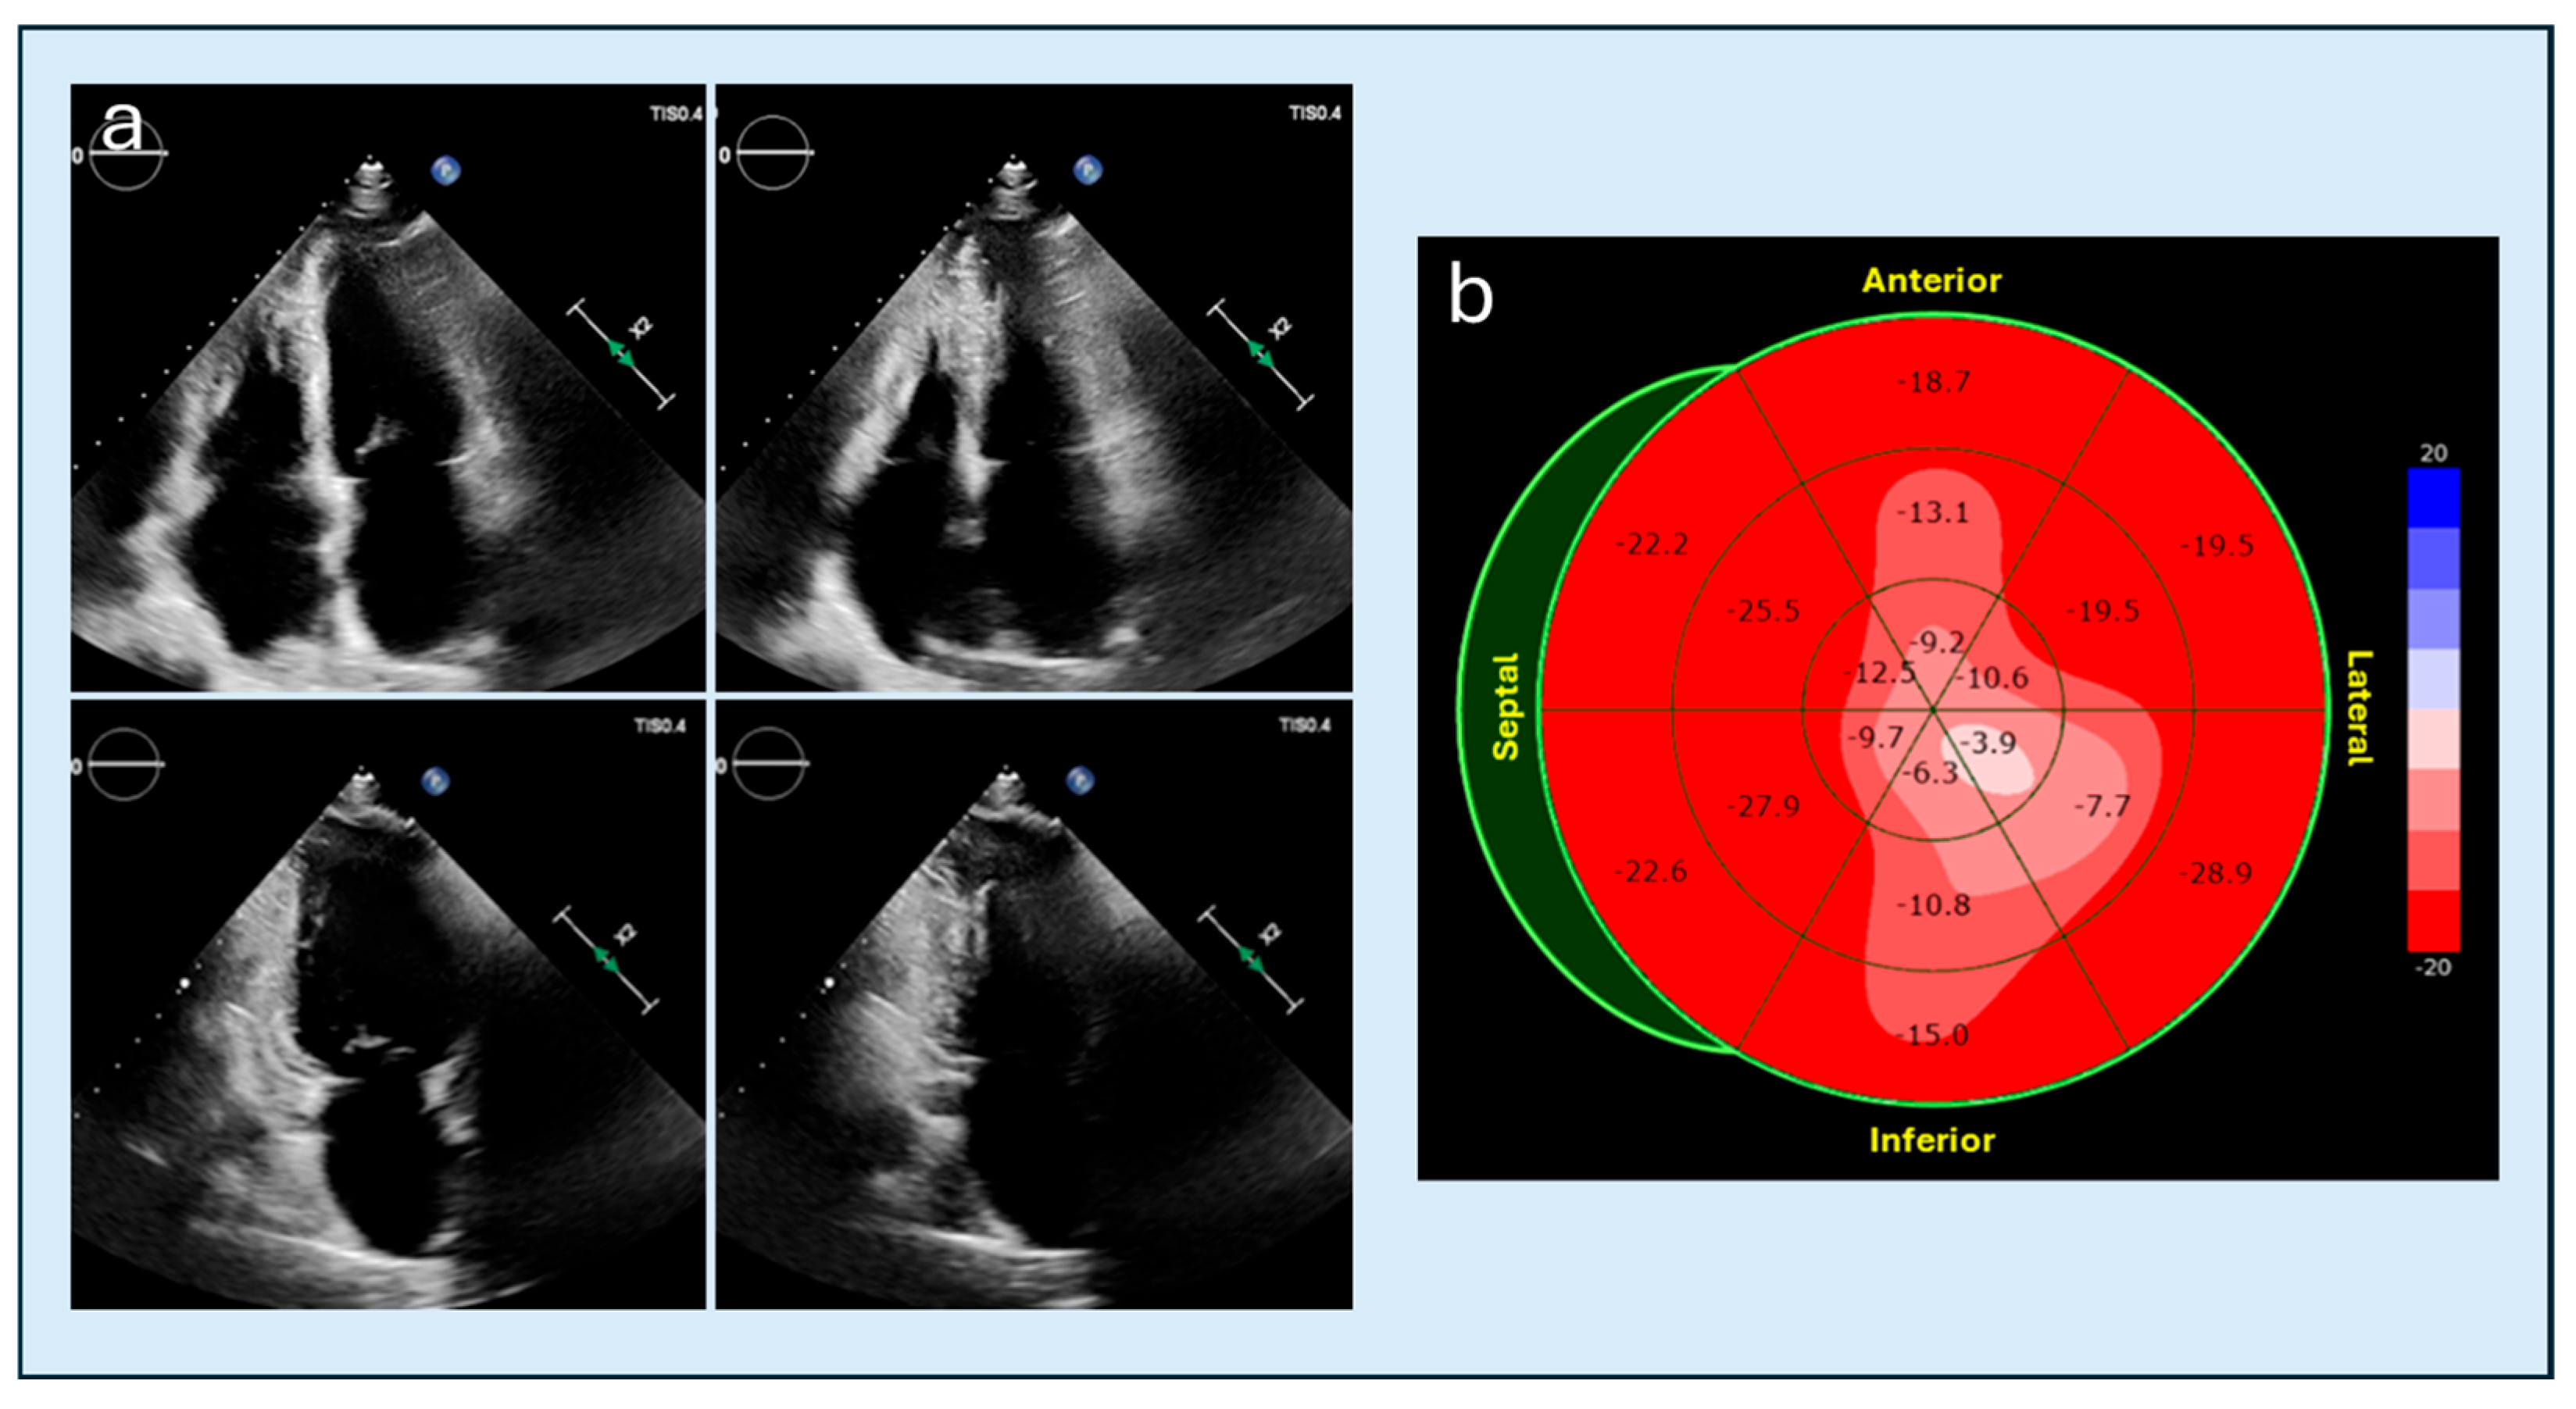

4.3. Speckle Tracking Imaging

- Saccheri, M.C.; Cianciulli, T.F.; Morita, L.A.; Méndez, R.J.; Beck, M.A.; Guerra, J.E.; Cozzarin, A.; Puente, L.J.; Balletti, L.R.; Lax, J.A. Speckle tracking echocardiography to assess regional ventricular function in patients with apical hypertrophic cardiomyopathy. World J. Cardiol. 2017, 9, 363–370. [Google Scholar] [CrossRef] [PubMed]

- Mihos, C.G.; Horvath, S.A.; Fernandez, R.; Escolar, E. Left ventricular strain and myocardial work in apical hypertrophic cardiomyopathy. J. Thorac. Dis. 2023, 15, 3197–3207. [Google Scholar] [CrossRef]